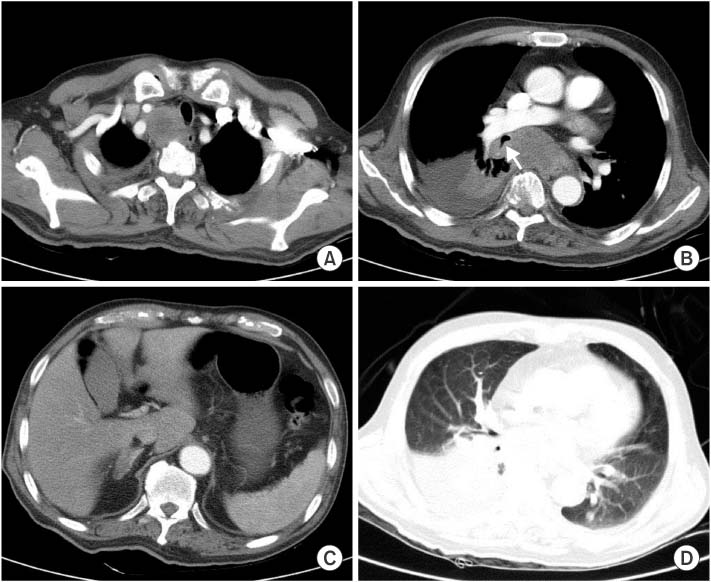

Fig. 1). Chest computed tomography (CT) scan revealed hugely enlarged upper paratracheal and subcarinal lymph nodes, an endobronchial mass associated with atelectasis of right lower lobe and pleural effusion at right hemithorax. Additionally two nodules in left lung and 2 cm-sized right adrenal mass suspicious of metastases were detected (

Fig. 2). Brain CT only showed mild ischemic changes of periventricular white matter and age-related atrophic changes. Considering the provisional diagnosis of lung cancer with sepsis due to obstructive pneumonia, a broad spectrum of antibiotics (piperacillin-tazobactam and moxifloxacin) was immediately administered with a supply of oxygen via mask. Bronchoscopy was then performed and demonstrated right vocal cord palsy and extrinsic compression of upper trachea. There were two endobronchial masses at right main bronchus, 3-cm apart from carina and at the orifice of right bronchus intermedius. The masses were about 1-2 cm sized, well-circumscribed hypervascular polypoid tumors (

Fig. 2Chest computed tomography scan. It reveals hugely enlarged upper paratracheal lymph node compressing trachea (A), and subcarinal lymph node and an endobronchial mass arrow associated with atelectasis of right lower lobe and pleural effusion (B). About 2 cm-sized right adrenal mass (C) and a metastatic nodule in left lower lung were also noted (D).